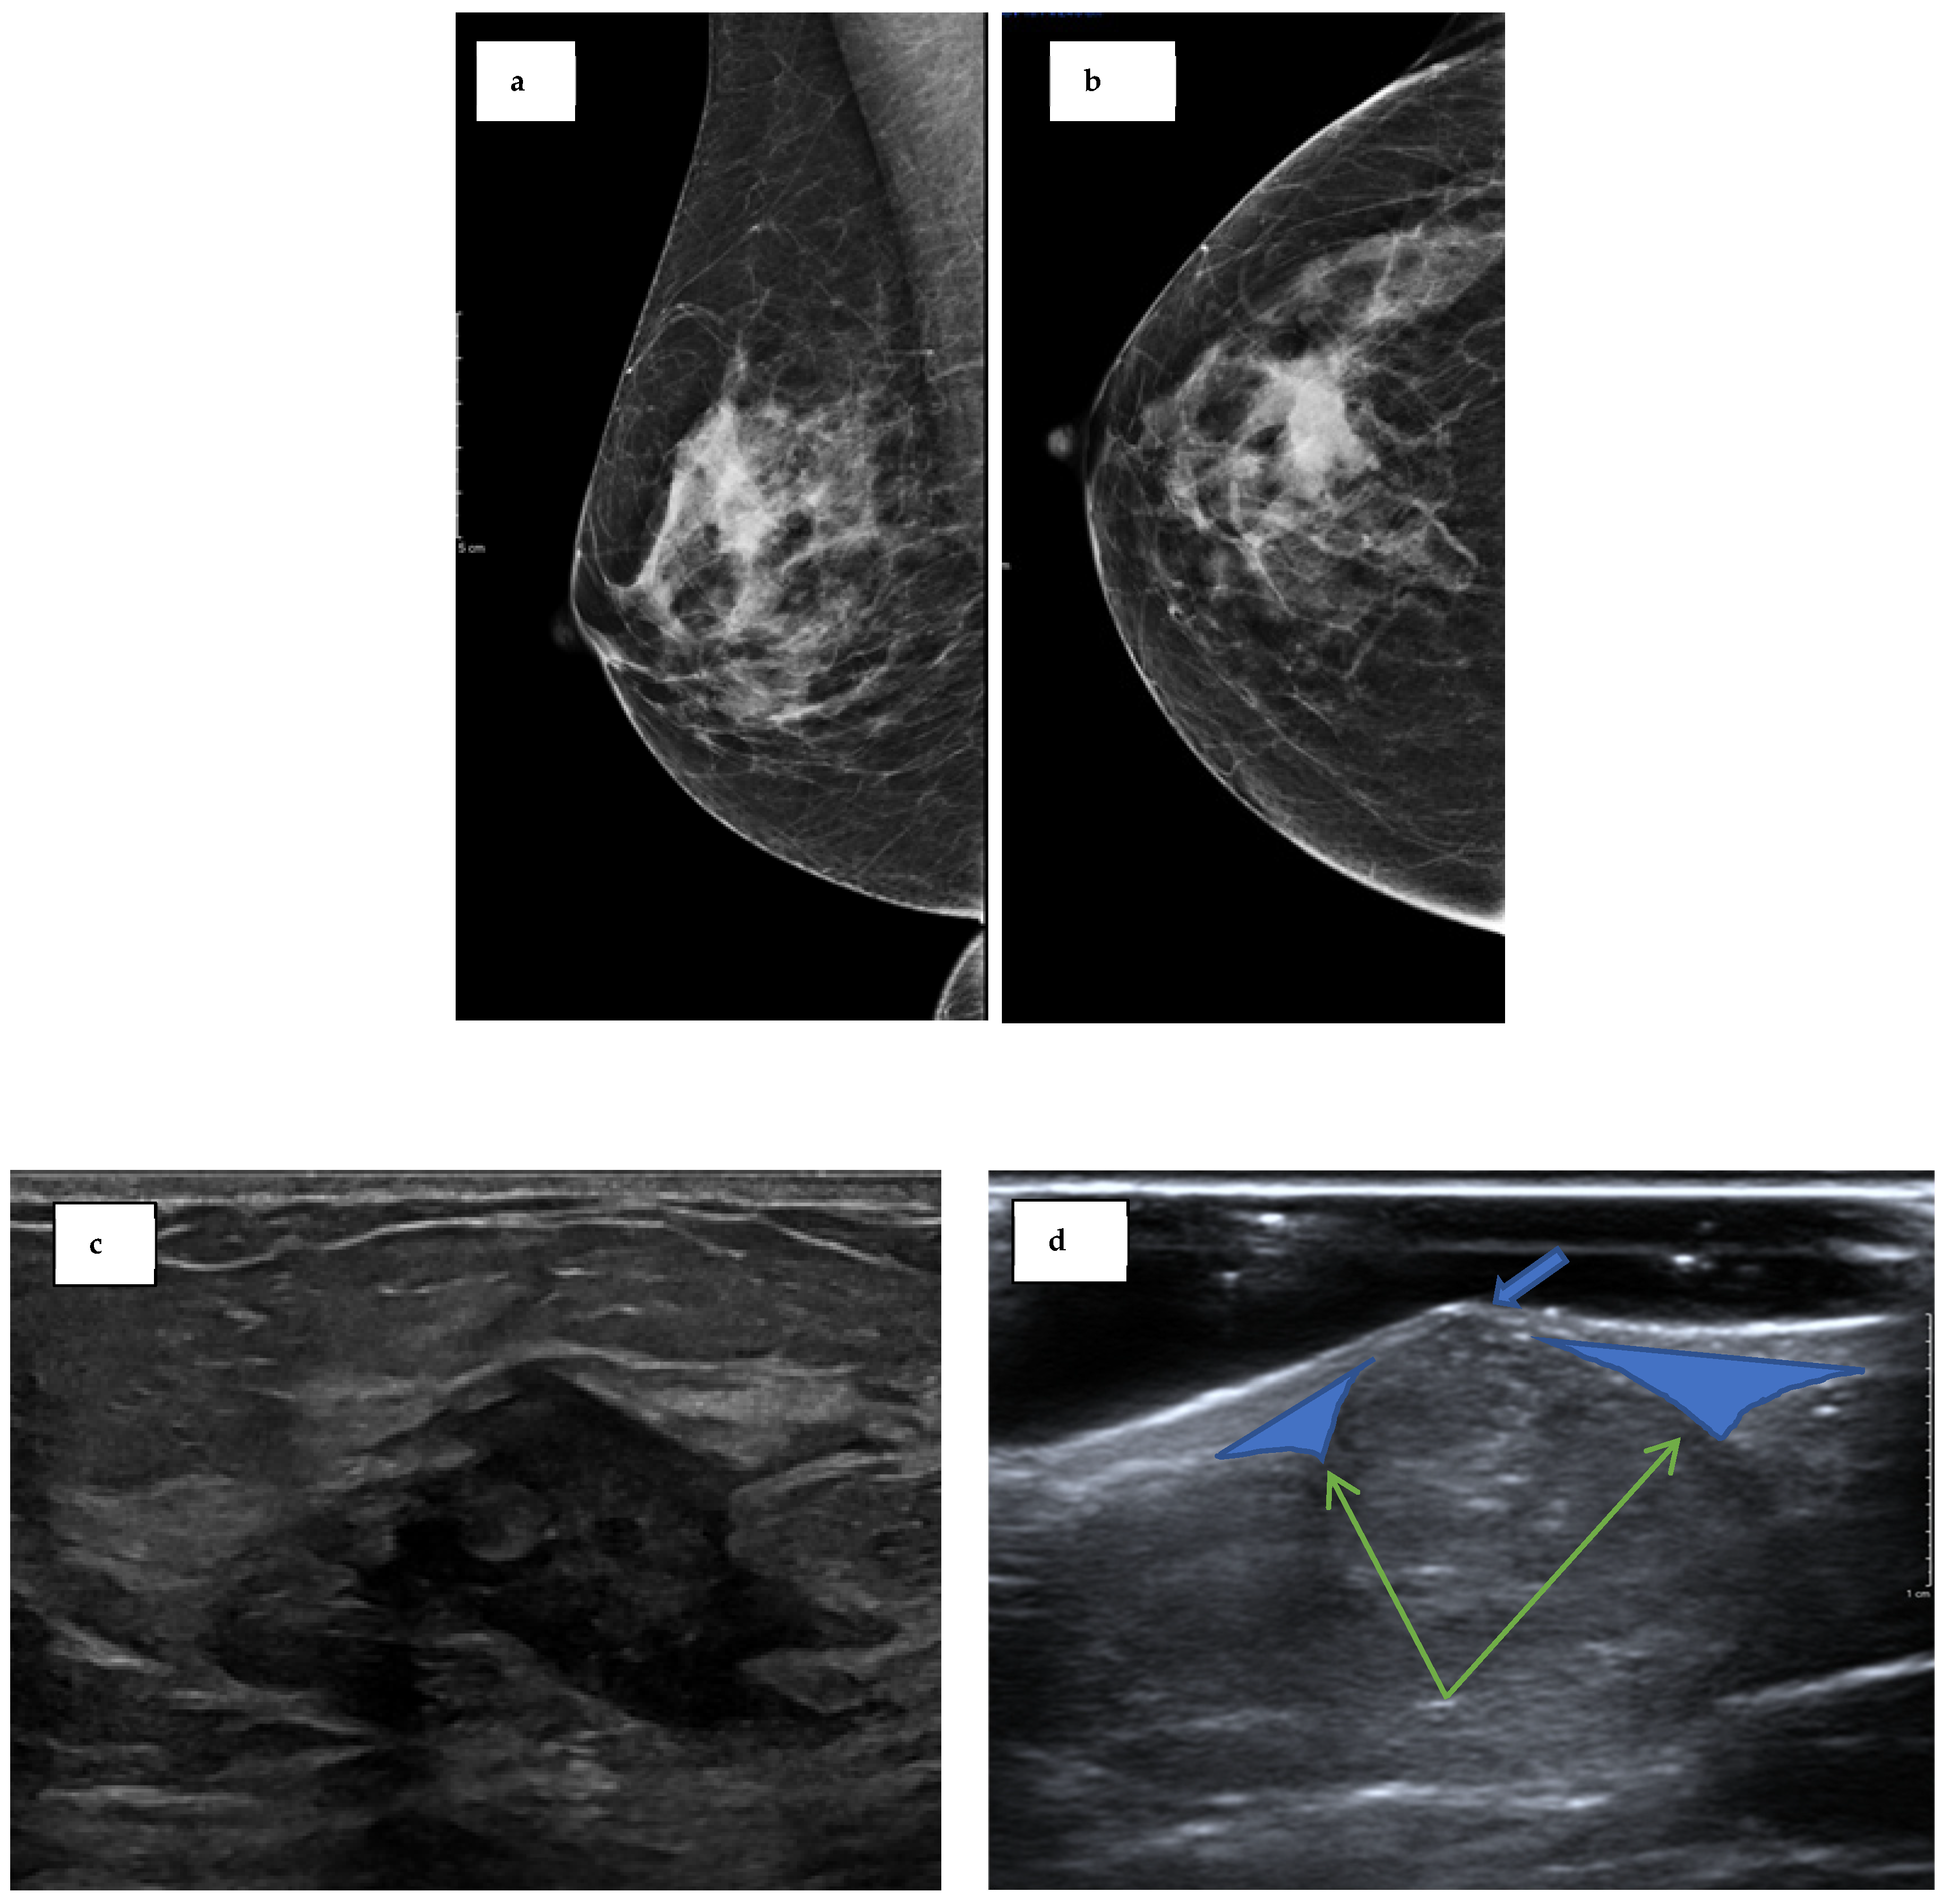

On clinical examination of the breast lump, a benign nodule (P2) was noted above the right nipple. A mammogram of the right breast showed a subtle, focal increase in density in the upper central breast. This was then visualised with tomosynthesis, which revealed an ill-defined mass lesion measuring 20 × 11 mm, superior and posterior to the nipple, which was radiologically malignant (M5) (Figure 1a,b). An ultrasound scan demonstrated an irregular hypoechoic mass measuring 25 × 20mm with malignant features (U5) (Figure 1c). An ultrasound-guided core biopsy was taken, and the biopsy confirmed a grade 3, invasive, triple-negative, no special type (NST) carcinoma. Following a multidisciplinary team discussion, she was offered bilateral (right therapeutic and left risk-reducing) mastectomy with right sentinel node biopsy in view of her history of Lynch syndrome.

Figure 1.

Radiological presentation. (a) Craniocaudal view of the right breast mammogram at symptomatic presentation. (b) Mediolateral oblique view of the right breast mammogram at symptomatic presentation. (c) Ultrasound of the right breast lump showing an irregular ill-defined malignant hypoechoic lesion (U5). (d) Ultrasound of the left breast mammographic finding. There is a punctum consistent with a sebaceous cyst (blue arrow). The claw sign (green arrows) finding indicates the lesion arose from the skin and not the breast.

Two years prior to the presentation, the patient had also noted a dark spot near the inferior mammary fold of her left (contralateral) breast. A subsequent screening mammography and ultrasound concluded that the lesion represented a benign sebaceous cyst (Figure 1d). A biopsy was not performed due to its typical characteristics of a sebaceous cyst and concern over an inflammatory response in the surrounding tissue following rupture [10]. After discussion with the patient regarding the surgical options, including breast-conserving surgery followed by radiotherapy or mastectomy, the patient opted for a bilateral mastectomy, with her history of Lynch syndrome being the main indication.